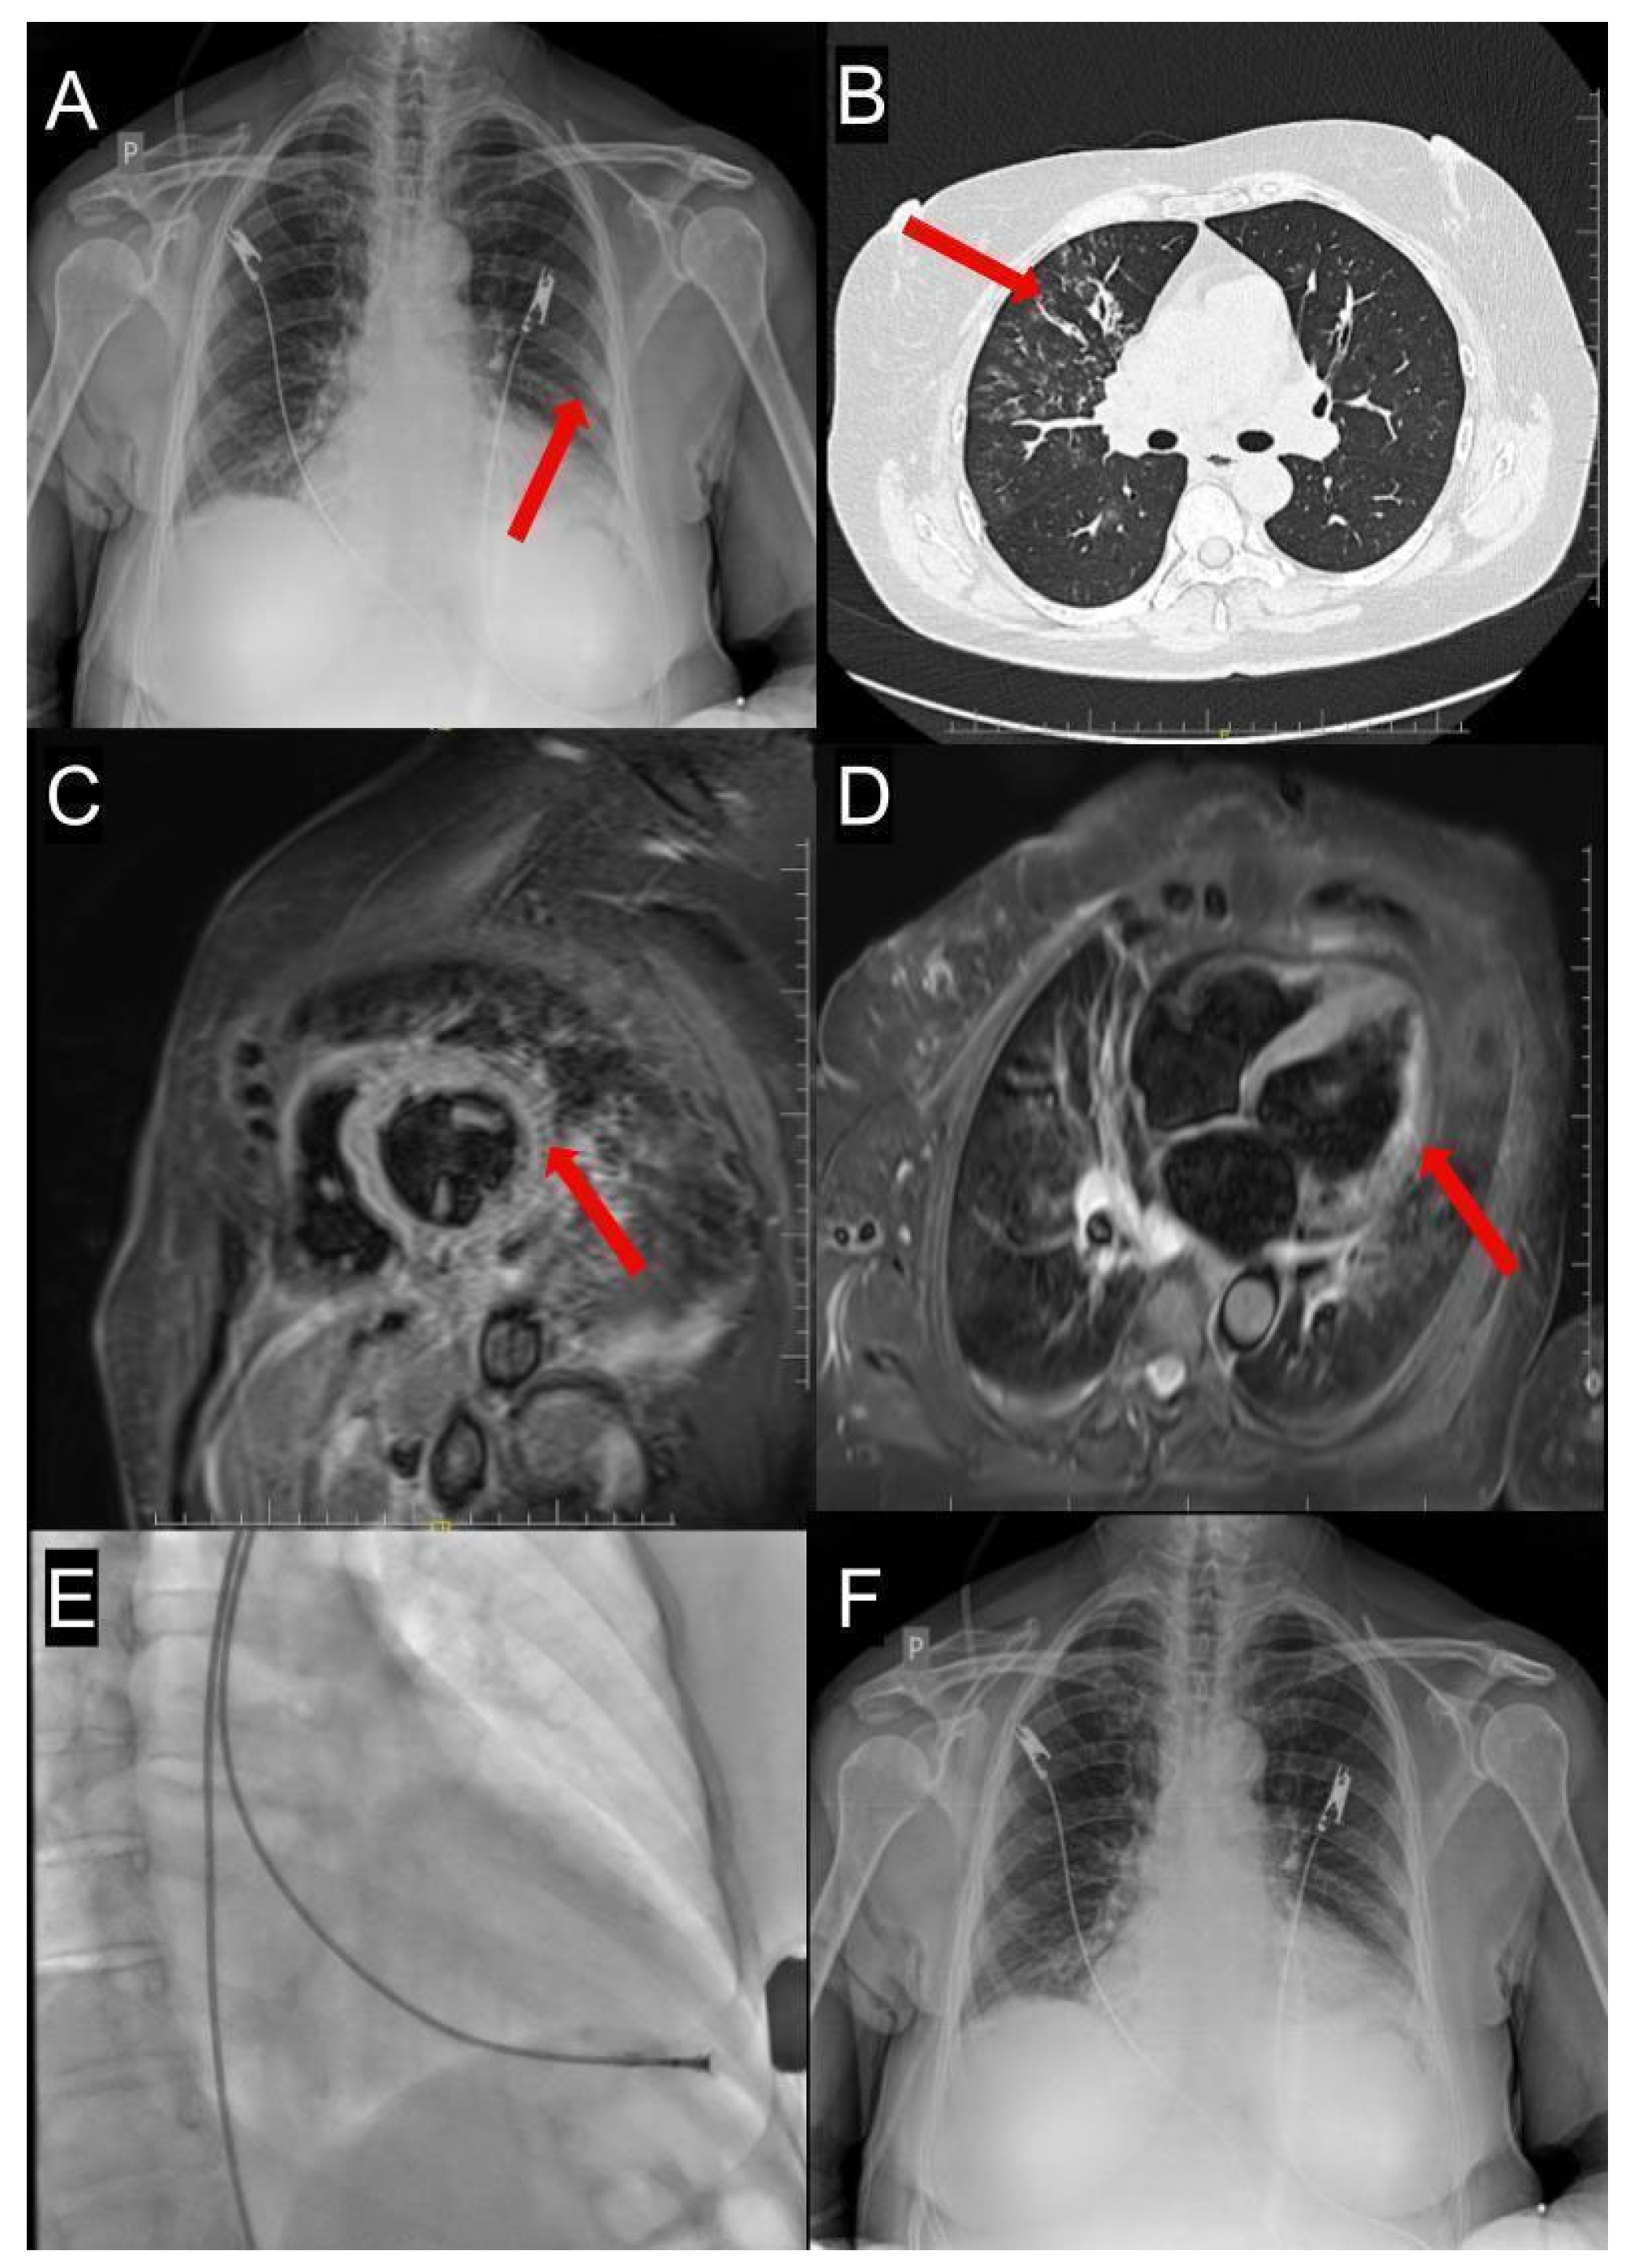

2. An Illustrative Case Report